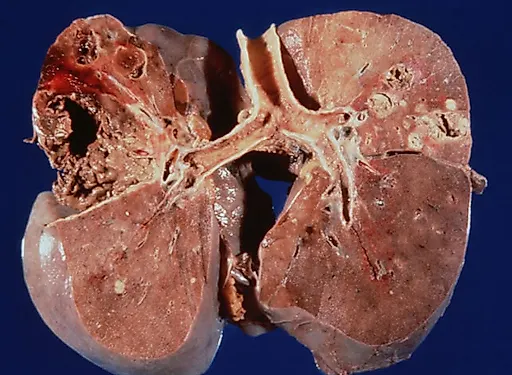

Инфекции мочевыводящих путей – состояние инфицирования мочевыводящего тракта микрофлорой, которая вызывает его воспаление.Различают инфекцию верхних (пиелонефрит) и нижних мочевых путей (цистит, простатит, уретрит) по наличию или отсутствию симптомов (симптоматическую или бессимптомную бак-териурию), по происхождению инфекции (внебольничную или нозокомиальную), осложненные и неосложненные.

Осложненные инфекции сопровождаются функциональными или анатомическими аномалиями верхних или нижних мочевых путей.